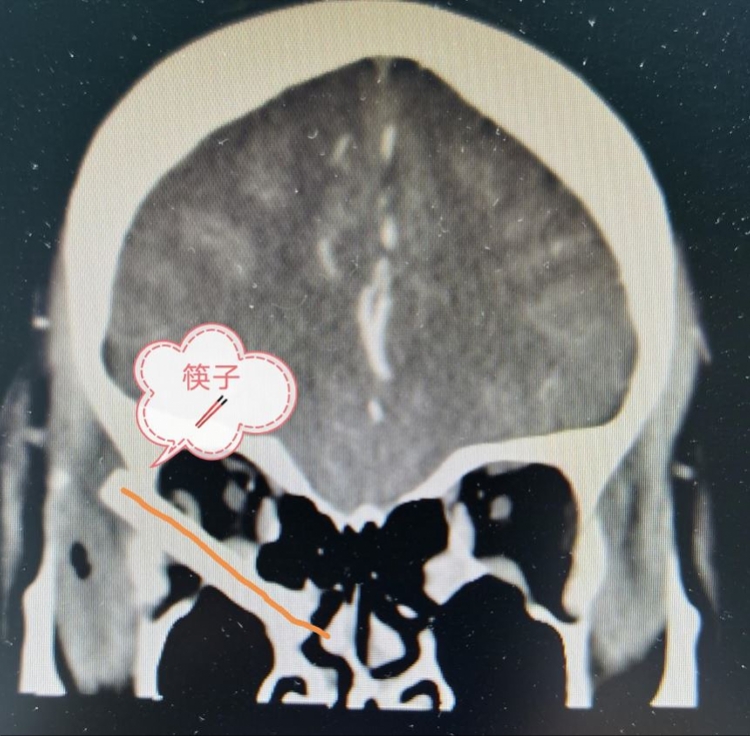

2月19日下午,他们迎来一名急诊患者。这名女患者因不慎被筷子插入眼眶内鼻窦,眼眶肿胀视力模糊,从湛江来到中山一院急诊求治,经诊断发现,筷子没入眶内3厘米,折断留在头颅内里的筷子有7厘米长。筷子从右颞部眶外侧戳入,向前下方穿透眼眶、筛窦、戳破鼻中隔、到达对侧筛窦。

据悉,造成女患者如此惊险一幕的,正是她家的熊孩子,当时,小孩在玩耍筷子,一不小心伤害了妈妈,庆幸的是,女患者没有伤及视神经和颅脑,没有造成失明和颅内出血。

经医院会诊,专家们认为,必须进行紧急手术,取出筷子,防止并发症发生同时保护视力。医护人员迅速对患者进行“新冠肺炎感染”排查,确认无感染后在急诊安排了手术。经过全身麻醉,鼻内镜和眶外联合手术后,专家们顺利取出异物。

据悉,术后,患者视力有所提高,没有复视和颅内并发症,目前正在康复当中。